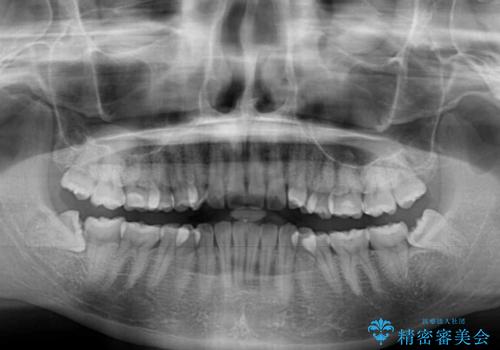

- 前歯のデコボコを治したいとのことで来院された患者様です。

上下顎ともに歯列全体の後方移動とIPR(歯と歯の間を削る)によってデコボコが解消するように設計し、インビザラインにより治療を行うこととしました。